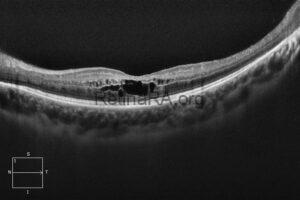

CRX-Related Occult Macular Dystrophy

A 34-year-old female patient presented with a 7–8-year history of progressively worsening vision and increasing [...]